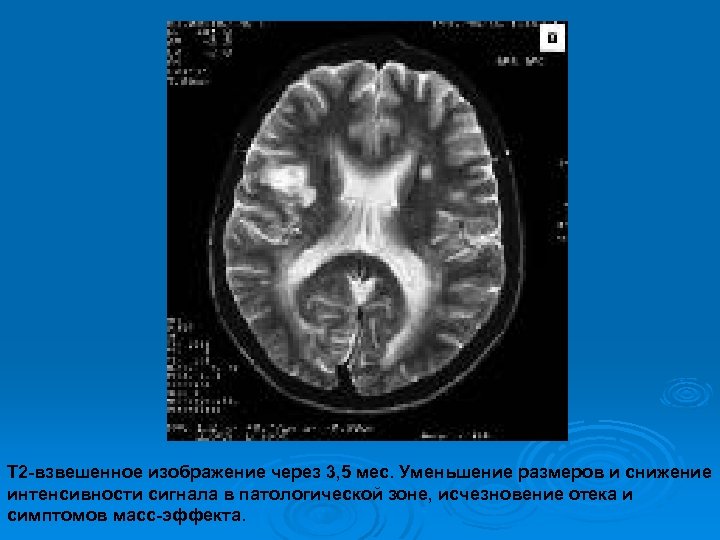

Изменения МРТ на фоне гормональной терапии

Т 2 -взвешенное изображение через 3, 5 мес. Уменьшение размеров и снижение интенсивности сигнала в патологической зоне, исчезновение отека и симптомов масс-эффекта.